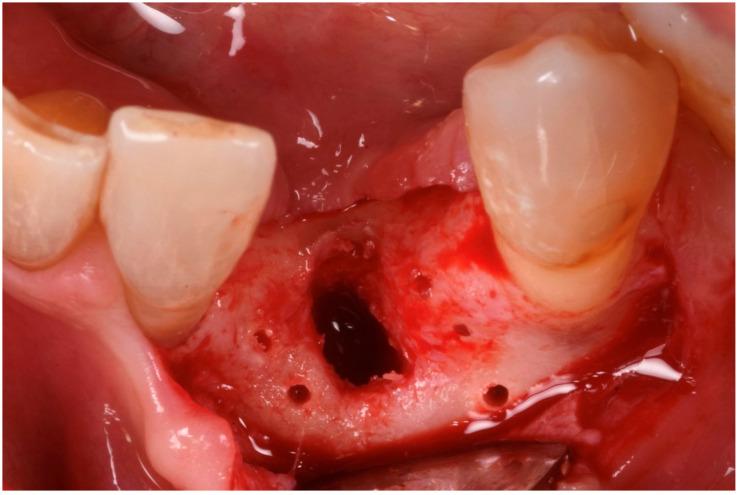

Guided bone regeneration (GBR) has represented a challenge for clinicians in the past 30 years, and the literature has well described many different surgical options such as d-PTFE membranes, titanium grids, or autogenous bone harvested from the posterior mandible. All of the previously mentioned techniques have shown a high rate of complications but, in the last decade, a new membrane made of xenogenic bone was introduced. Most of the publications regarding its application report very few and mild complications. In this article we will suggest a new application using segmented xenogenic bone sheets instead of autogenous bone to correct severe ridge deformity. : Xenogenic bone sheets have been studied extensively over the past decade and have proven effective, with a very low rate of complications when used to reconstruct bone atrophies. The technique presented in this paper aims to reduce morbidity, avoid the need for intra-oral graft harvesting, and minimize both surgical time and post-operative discomfort. : Xenogenic bone sheets of equine origin were used to reconstruct severe 3D bone defects in five patients requiring dental implants. The segmentation of the sheet allowed the operator to rebuild the missing bone walls and achieve optimal anatomy without compromise. Furthermore, using different sizes and thicknesses of the bone sheets allowed safe procedures preventing early exposure of the membranes. CBCT of the defects before and after 8 months of healing were measured with Exocad software to assess the volumetric gain. Histological analysis performed on one site showed integration of the bone lamina and live bone underneath. : In all five cases evaluated the ridge deformities were successfully corrected and all patients' implants have functioned for more than two years to date. The average horizontal bone gain in these five cases was 6.18 mm (±1.19 mm) while the vertical gain was 9.70 mm (±2.39 mm). : This new application of flex cortical sheets simplifies the surgical procedure for both operator and patient, reduces morbidity and post-operative complications, and shows promising signs for resolving complex 3D bone reconstructions.

在过去30年里,引导骨再生(GBR)一直是临床医生面临的一项挑战,文献中已经详细描述了许多不同的手术选择,如双层聚四氟乙烯(d-PTFE)膜、钛网或从下颌后部获取的自体骨。上述所有技术都显示出较高的并发症发生率,但在过去十年中,一种由异种骨制成的新型膜被引入。关于其应用的大多数出版物报告的并发症很少且很轻微。在本文中,我们将提出一种使用分段异种骨片代替自体骨来矫正严重牙槽嵴畸形的新应用。:在过去十年中,异种骨片已被广泛研究,并已被证明是有效的,用于重建骨萎缩时并发症发生率非常低。本文介绍的技术旨在降低发病率,避免口内取骨的需要,并将手术时间和术后不适降至最低。:使用马源异种骨片为五名需要种植牙的患者重建严重的三维骨缺损。骨片的分段使手术者能够重建缺失的骨壁并实现最佳解剖结构而不受影响。此外,使用不同尺寸和厚度的骨片可进行安全操作,防止膜过早暴露。使用Exocad软件测量愈合8个月前后缺损的锥形束计算机断层扫描(CBCT),以评估体积增加情况。对一个部位进行的组织学分析显示骨板与下方活骨的整合。:在评估的所有五例病例中,牙槽嵴畸形均得到成功矫正,所有患者的种植体至今已正常使用两年多。这五例病例的平均水平骨增量为6.18毫米(±1.19毫米),而垂直增量为9.70毫米(±2.39毫米)。:这种柔性皮质骨片的新应用简化了手术者和患者的手术过程,降低了发病率和术后并发症,并显示出解决复杂三维骨重建问题的良好前景。